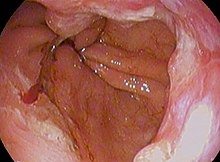

Both macroscopic (from endoscopy) and microscopic positive findings are required to make a diagnosis. Barrett's esophagus is marked by the presence of columnar epithelia in the lower esophagus, replacing the normal squamous cell epithelium—an example of metaplasia. The secretory columnar epithelium may be more able to withstand the erosive action of the gastric secretions; however, this metaplasia confers an increased risk of adenocarcinoma.[15]

Screening endoscopy is recommended among males over the age of 60 who have reflux symptoms that are of long duration and not controllable with treatment.[16] Among those not expected to live more than 5 years screening is not recommended.[16]

The Seattle protocol is used commonly in endoscopy to obtain endoscopic biopsies for screening, taken every 1-2 cm from the gastroesophageal junction.